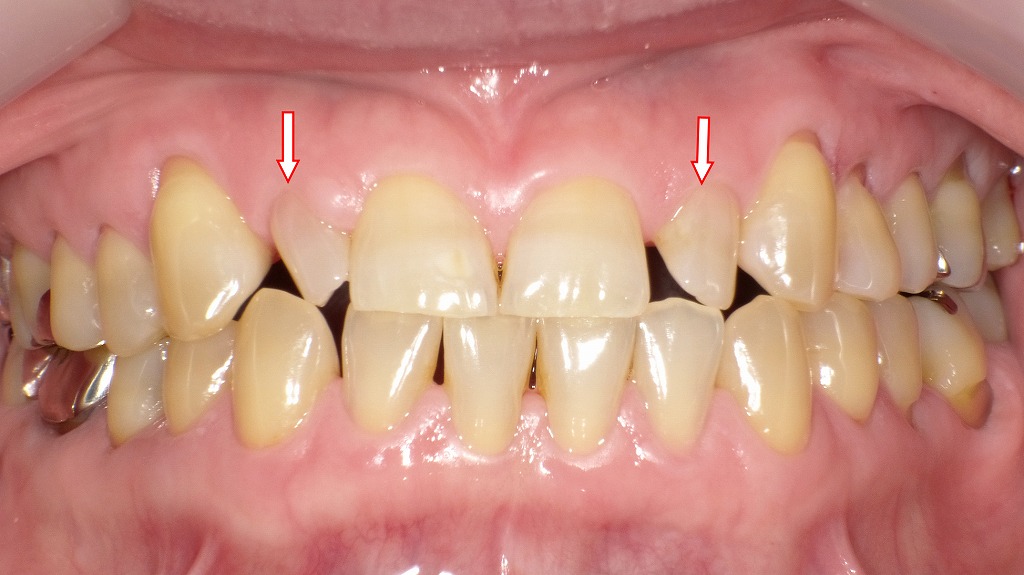

正面観:歯が小さい症例

この画像は、歯列を正面から撮影した口腔内写真です。赤い矢印で示されているのは、上顎側切歯(2番)の部分です。

■ 上顎側切歯(2番)が小さい(矮小歯)

左右の上顎2番(矢印部分)は、通常よりも小さく形成されています。

このような歯を**矮小歯(わいしょうし)**と呼びます。

形が円錐状または細長くなることが多く、先端が尖って見えるのが特徴です。

■ 隙間(空隙歯列)

2番が小さいため、その隣の前歯(中切歯:1番)や犬歯(3番)との間に**隙間(空隙)**が生じています。

これは歯の大きさと顎の幅のバランスが取れていないために起こります。